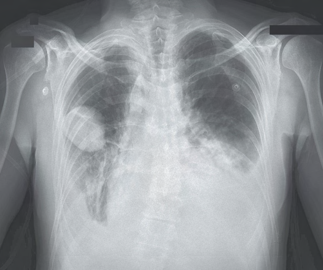

Recent studies indicate that Generative Pre-trained Transformer 4 with Vision (GPT-4V) outperforms human physicians in medical challenge tasks. However, these evaluations primarily focused on the accuracy of multi-choice questions alone. Our study extends the current scope by conducting a comprehensive analysis of GPT-4V's rationales of image comprehension, recall of medical knowledge, and step-by-step multimodal reasoning when solving New England Journal of Medicine (NEJM) Image Challenges - an imaging quiz designed to test the knowledge and diagnostic capabilities of medical professionals. Evaluation results confirmed that GPT-4V outperforms human physicians regarding multi-choice accuracy (88.0% vs. 77.0%, p=0.034). GPT-4V also performs well in cases where physicians incorrectly answer, with over 80% accuracy. However, we discovered that GPT-4V frequently presents flawed rationales in cases where it makes the correct final choices (27.3%), most prominent in image comprehension (21.6%). Regardless of GPT-4V's high accuracy in multi-choice questions, our findings emphasize the necessity for further in-depth evaluations of its rationales before integrating such models into clinical workflows.